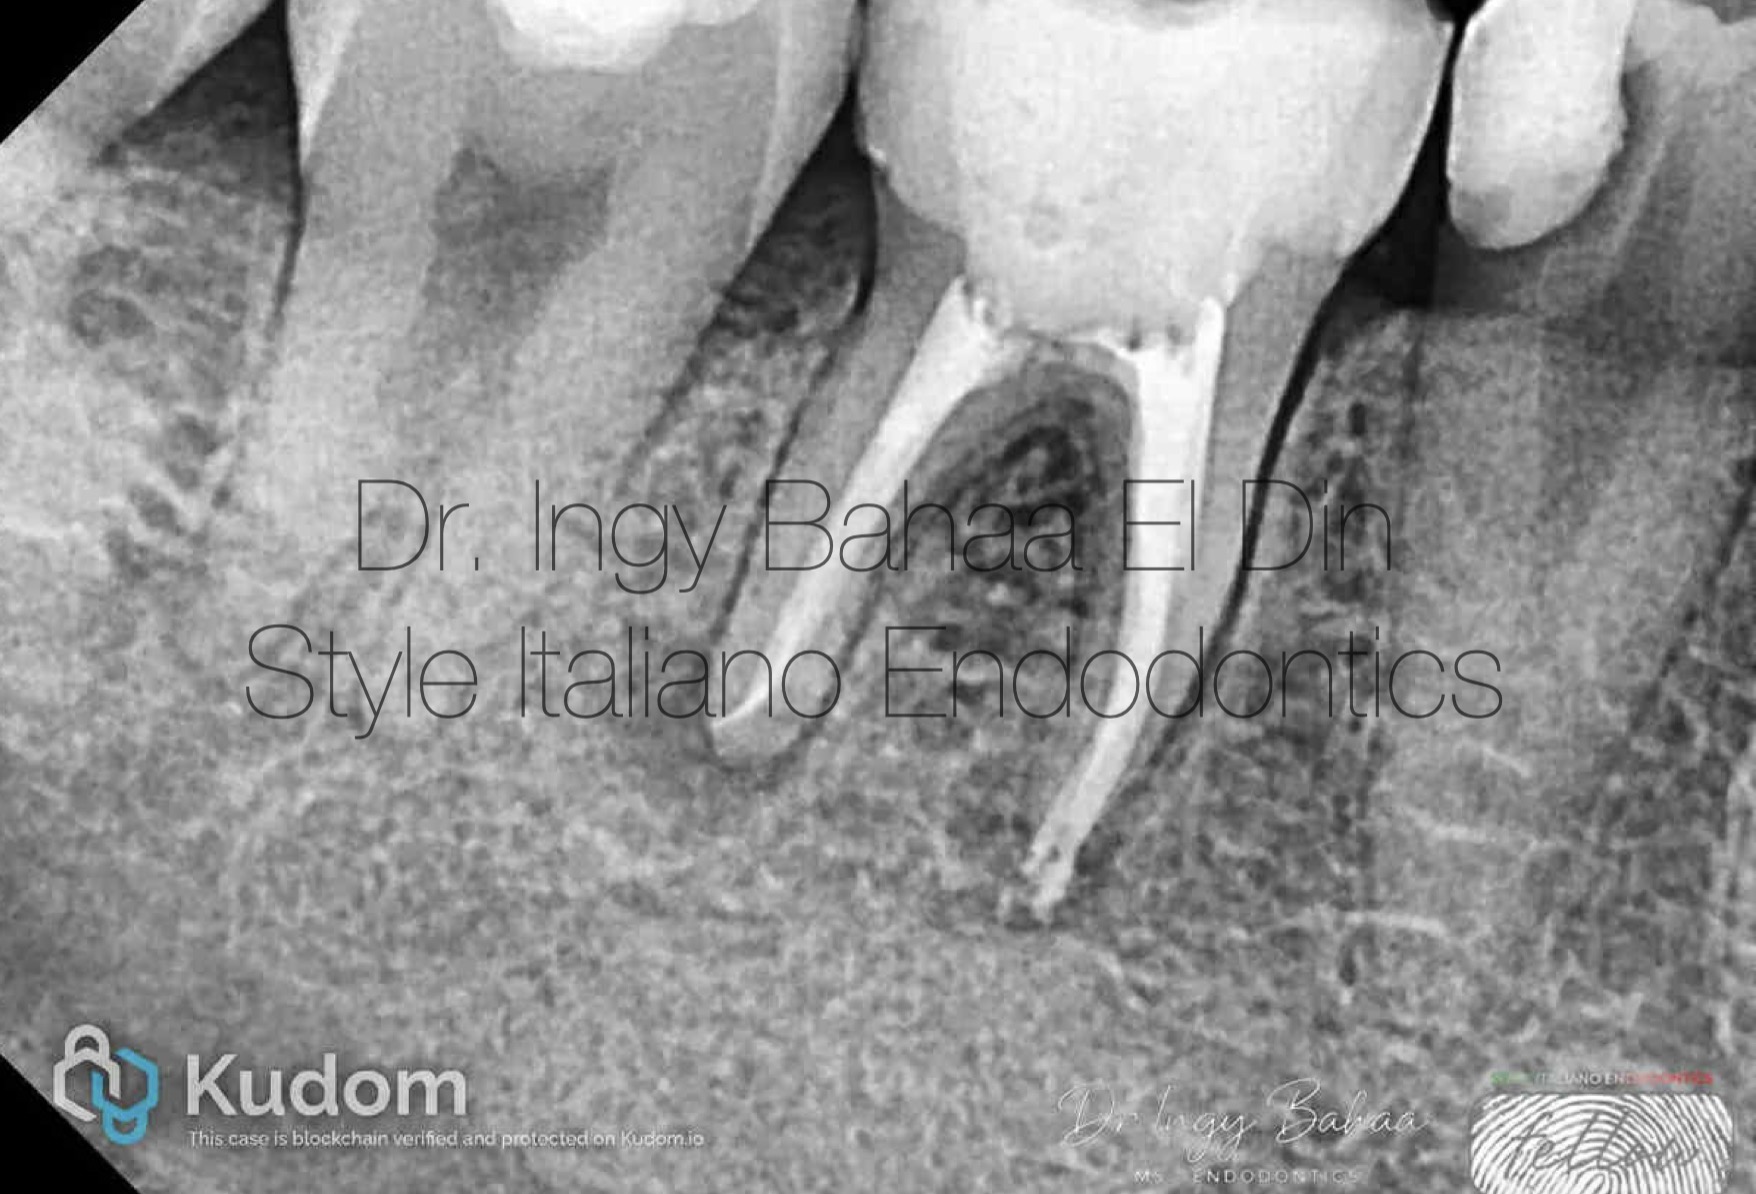

Fig. 2

CBCT Sagittal cuts shows a more defined abscess and precise location of the broken files. First file separated in mesio buccal canal above the curve , and the second file separated in Distal Canal almost at the end of apical foramen and the low contrast predicts it to be a 10 or 15 k file.